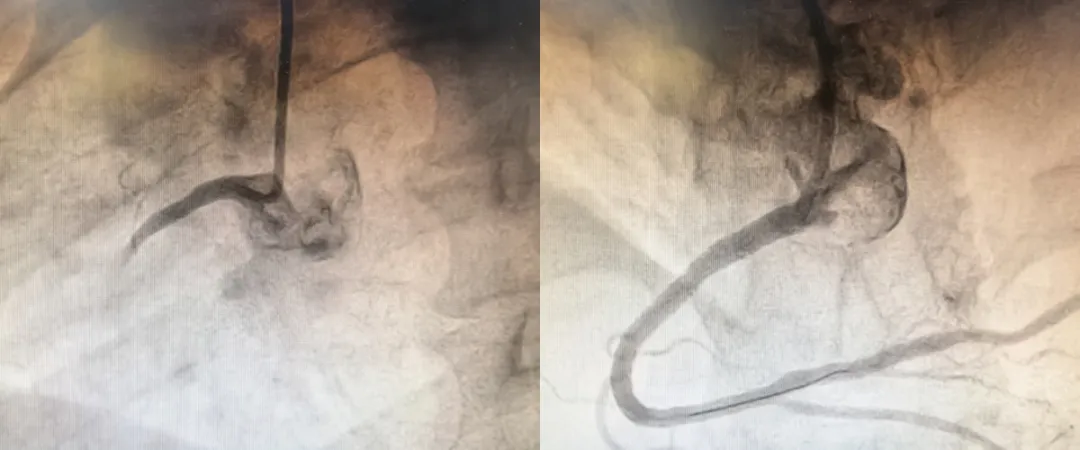

术中血管造影图像

与此同时,依托于苏州工业园区紧密性“医联体”的高效协作机制,星海医院与苏大附四院立刻启动转诊。患者的转运通知直达我院胸痛中心,导管室同步被激活,手术团队即刻集结待命。绿色通道一路畅通,从院前接诊到患者被无缝转接入院、直至安全送达导管室,整个过程没有耽误一秒宝贵的救治时间。苏州大学附属第四医院心内科学科带头人周亚峰教授带领我院心内科手术团队为患者顺利实施了急诊冠状动脉介入手术,迅速疏通了堵塞的心脏血管。术后,患者胸痛症状显著缓解,病情逐步趋于平稳。从120救援启动至血管疏通,全程仅用了不到1小时!